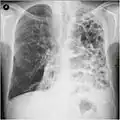

A chest X-ray is not useful to establish a diagnosis of COPD, but it is of use in either excluding other conditions or including comorbidities such as pulmonary fibrosis and bronchiectasis. Characteristic signs of COPD on X-ray include hyperinflation (shown by a flattened diaphragm and an increased retrosternal air space) and lung hyperlucency.[5] A saber-sheath trachea may also be shown that is indicative of COPD.[111]

Chest X-ray demonstrating severe COPD, displaying small heart size in comparison to the lungs

A lateral chest X-ray of a person with emphysema, displaying barrel chest and flat diaphragm